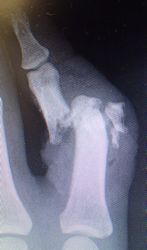

30歳男。東京都八丈島

2014年12月29日,ワイヤーに左示指を巻き込まれて不全切断受傷。〇〇病院を受診し,直ちに△△病院に救急ヘリ搬送され,形成外科で緊急手術(再接着術)となったが,生着せず,手掌部で切断⇒断端形成の予定だったが,患者の叔母(東京在住)がカンボジアで湿潤治療をしているKEN CLINICの奥澤先生と知り合いだったため,当科で一度診てもらったほうがいいとアドバイスされ,セカンドオピニオンで当科を受診。

当初はラップで被覆(ワイヤーのためにプラスモイストではうまく覆えなかった)。1月21日,22日にワイヤー抜去。3月に入ってから突出した骨を骨鉗子で切除(無麻酔で大丈夫だった)。3月19日,八丈島に戻った。